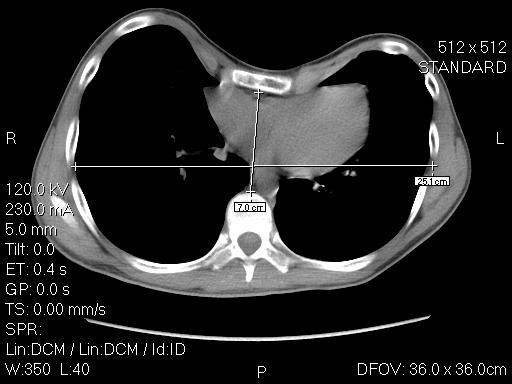

診斷為漏斗胸CT。

漏斗胸不能預防,只能越早發現越早就醫。X光計算漏斗胸指數,即胸壁橫徑與前後徑比值被視為治療決定的分水嶺。根據指引,漏斗胸指數若超過3.25的患者、有心肺功能影響或心理障碍的患者,視為嚴重,需要考慮手術治療。 漏斗胸指數小於3.25的輕度患者,則建議採用保守治療。